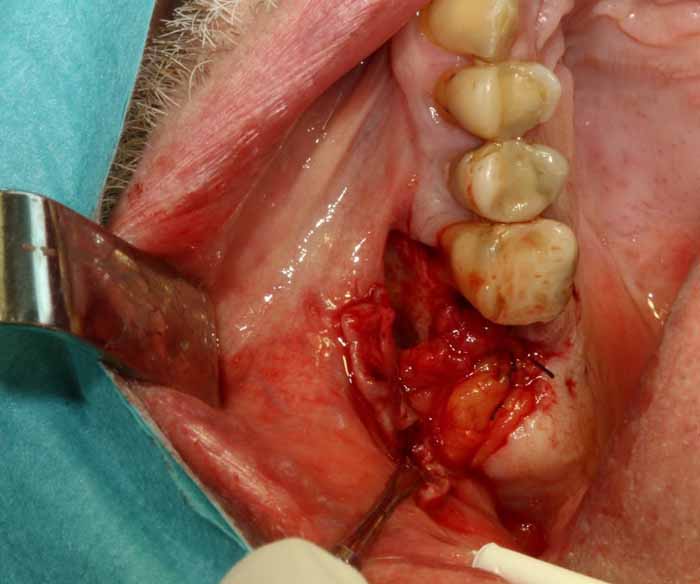

治療

慢性副鼻腔炎の治療には、歯の感染の除去が含まれます。これには、歯内療法、歯周治療、または外科的な処置による抜歯が必要になる場合があります。感染の予防が困難な場合は、抜歯が必要になる場合があります。その後、副鼻腔の交通を特定するために、Vamevalテストを実施する必要があります。患者との良好なコミュニケーションが極めて重要であり、治癒を確実にするためには、より根本的な治療が必要になる場合が多いです。急性副鼻腔炎の場合は治療が必要です。PC予防と、ネザリルなどの充血除去薬を組み合わせた、1回限りの手術が行われる。より大きな交通や瘻孔が慢性化している場合は、鼻の矯正手術(画像4a~4e)が必要となります。場合によっては、耳鼻咽喉科医によるFESS手術と同時に行うこともできます。FESS手術では、鼻の側壁にある開口部を外科的に広げて換気を確保し、閉塞を防止します。

歯が原因となって菌の活動が活発になっていると思われる副鼻腔炎(保健センター/耳鼻咽喉科クリニックでのCT検査によって確認されたものなど)の場合、抜歯前に綿密な治療計画を立てる必要があります。抜歯後の副鼻腔閉鎖時に、副鼻腔内にまだ膿性浸出物が残っており、活動性の感染症がある場合には、交通路の形成が優れた技術的品質で実施されたとしても治癒の条件は悪くなります。副鼻腔閉鎖時には、感染を軽減し、副鼻腔から膿性浸出物を除去する必要があります。これは、抜歯3日前に抗生物質治療を開始することで達成できます。抜歯中は、患者が座った状態で鼻/口から透明な液体だけが出てくるまで、生理食塩水で副鼻腔を洗浄します。

その後、高品質の副鼻腔手術を行うことができ、口腔上顎洞瘻が生じることなく、治癒するための条件が改善されています。